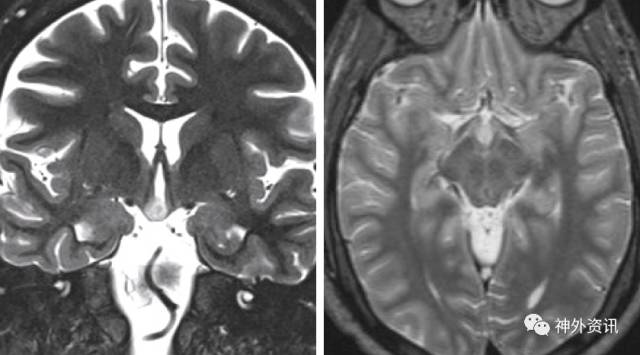

对于有癫痫发作的患者其诊断相关检查须包括MRI影像。下丘脑错构瘤的典型影像学特征为T2加权像较正常脑组织的明显强化信号。MRS波谱成像则通常表现为神经元密度的减少和胶质细胞的增加。

下丘脑错构瘤有两种亚型,根据肿瘤与正常下丘脑组织的解剖学关系区分。无基底型下丘脑错构瘤,其肿瘤底部主要位于其原发部位,并对周围正常下丘脑组织产生推挤。相对的,有基底型下丘脑错构瘤表现为以三脑室底部为基底在三脑室内悬浮。无基底型错构瘤更易引起癫痫发作,而有基底型则与内分泌功能障碍相关。

图1. 该图显示的是一名23岁男性患者,表现以痴笑型癫痫为主的难治性多灶性癫痫,磁共振检查提示为一无基底错构瘤,其T2序列呈现高信号,病灶表现为沿三脑室前壁生长的不增强团块影。